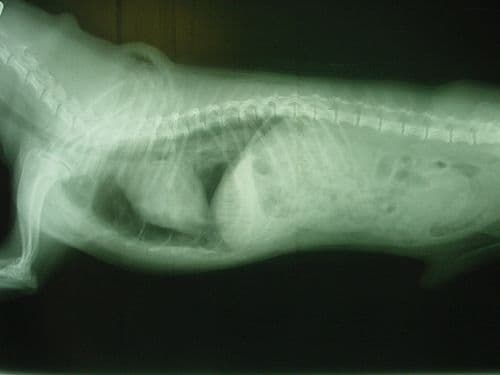

#légmell

#mellkas

Légmell